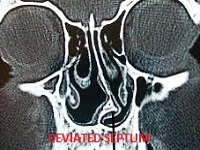

Deviated Nasal Septum:

Nasal Septum is the midline partition between two nostrils of nose. Virtually, more than 70% of human beings have a deviated Nasal Septum. It doesn’t always require treatment unless it cause any of the below mentioned symptoms like:

It is treated by a surgery called Septoplasty. Conventionally it was done with the help of traditional headlights and instruments. In today’s era, it can be corrected by a minimally invasive method called as Endoscopic Septoplasty. It has got all the advantages of minimal invasive therapy (like Laparoscopy for abdominal surgeries). Consult the Best ENT Doctor / ENT Specialist near you for endoscopic Septoplasty.